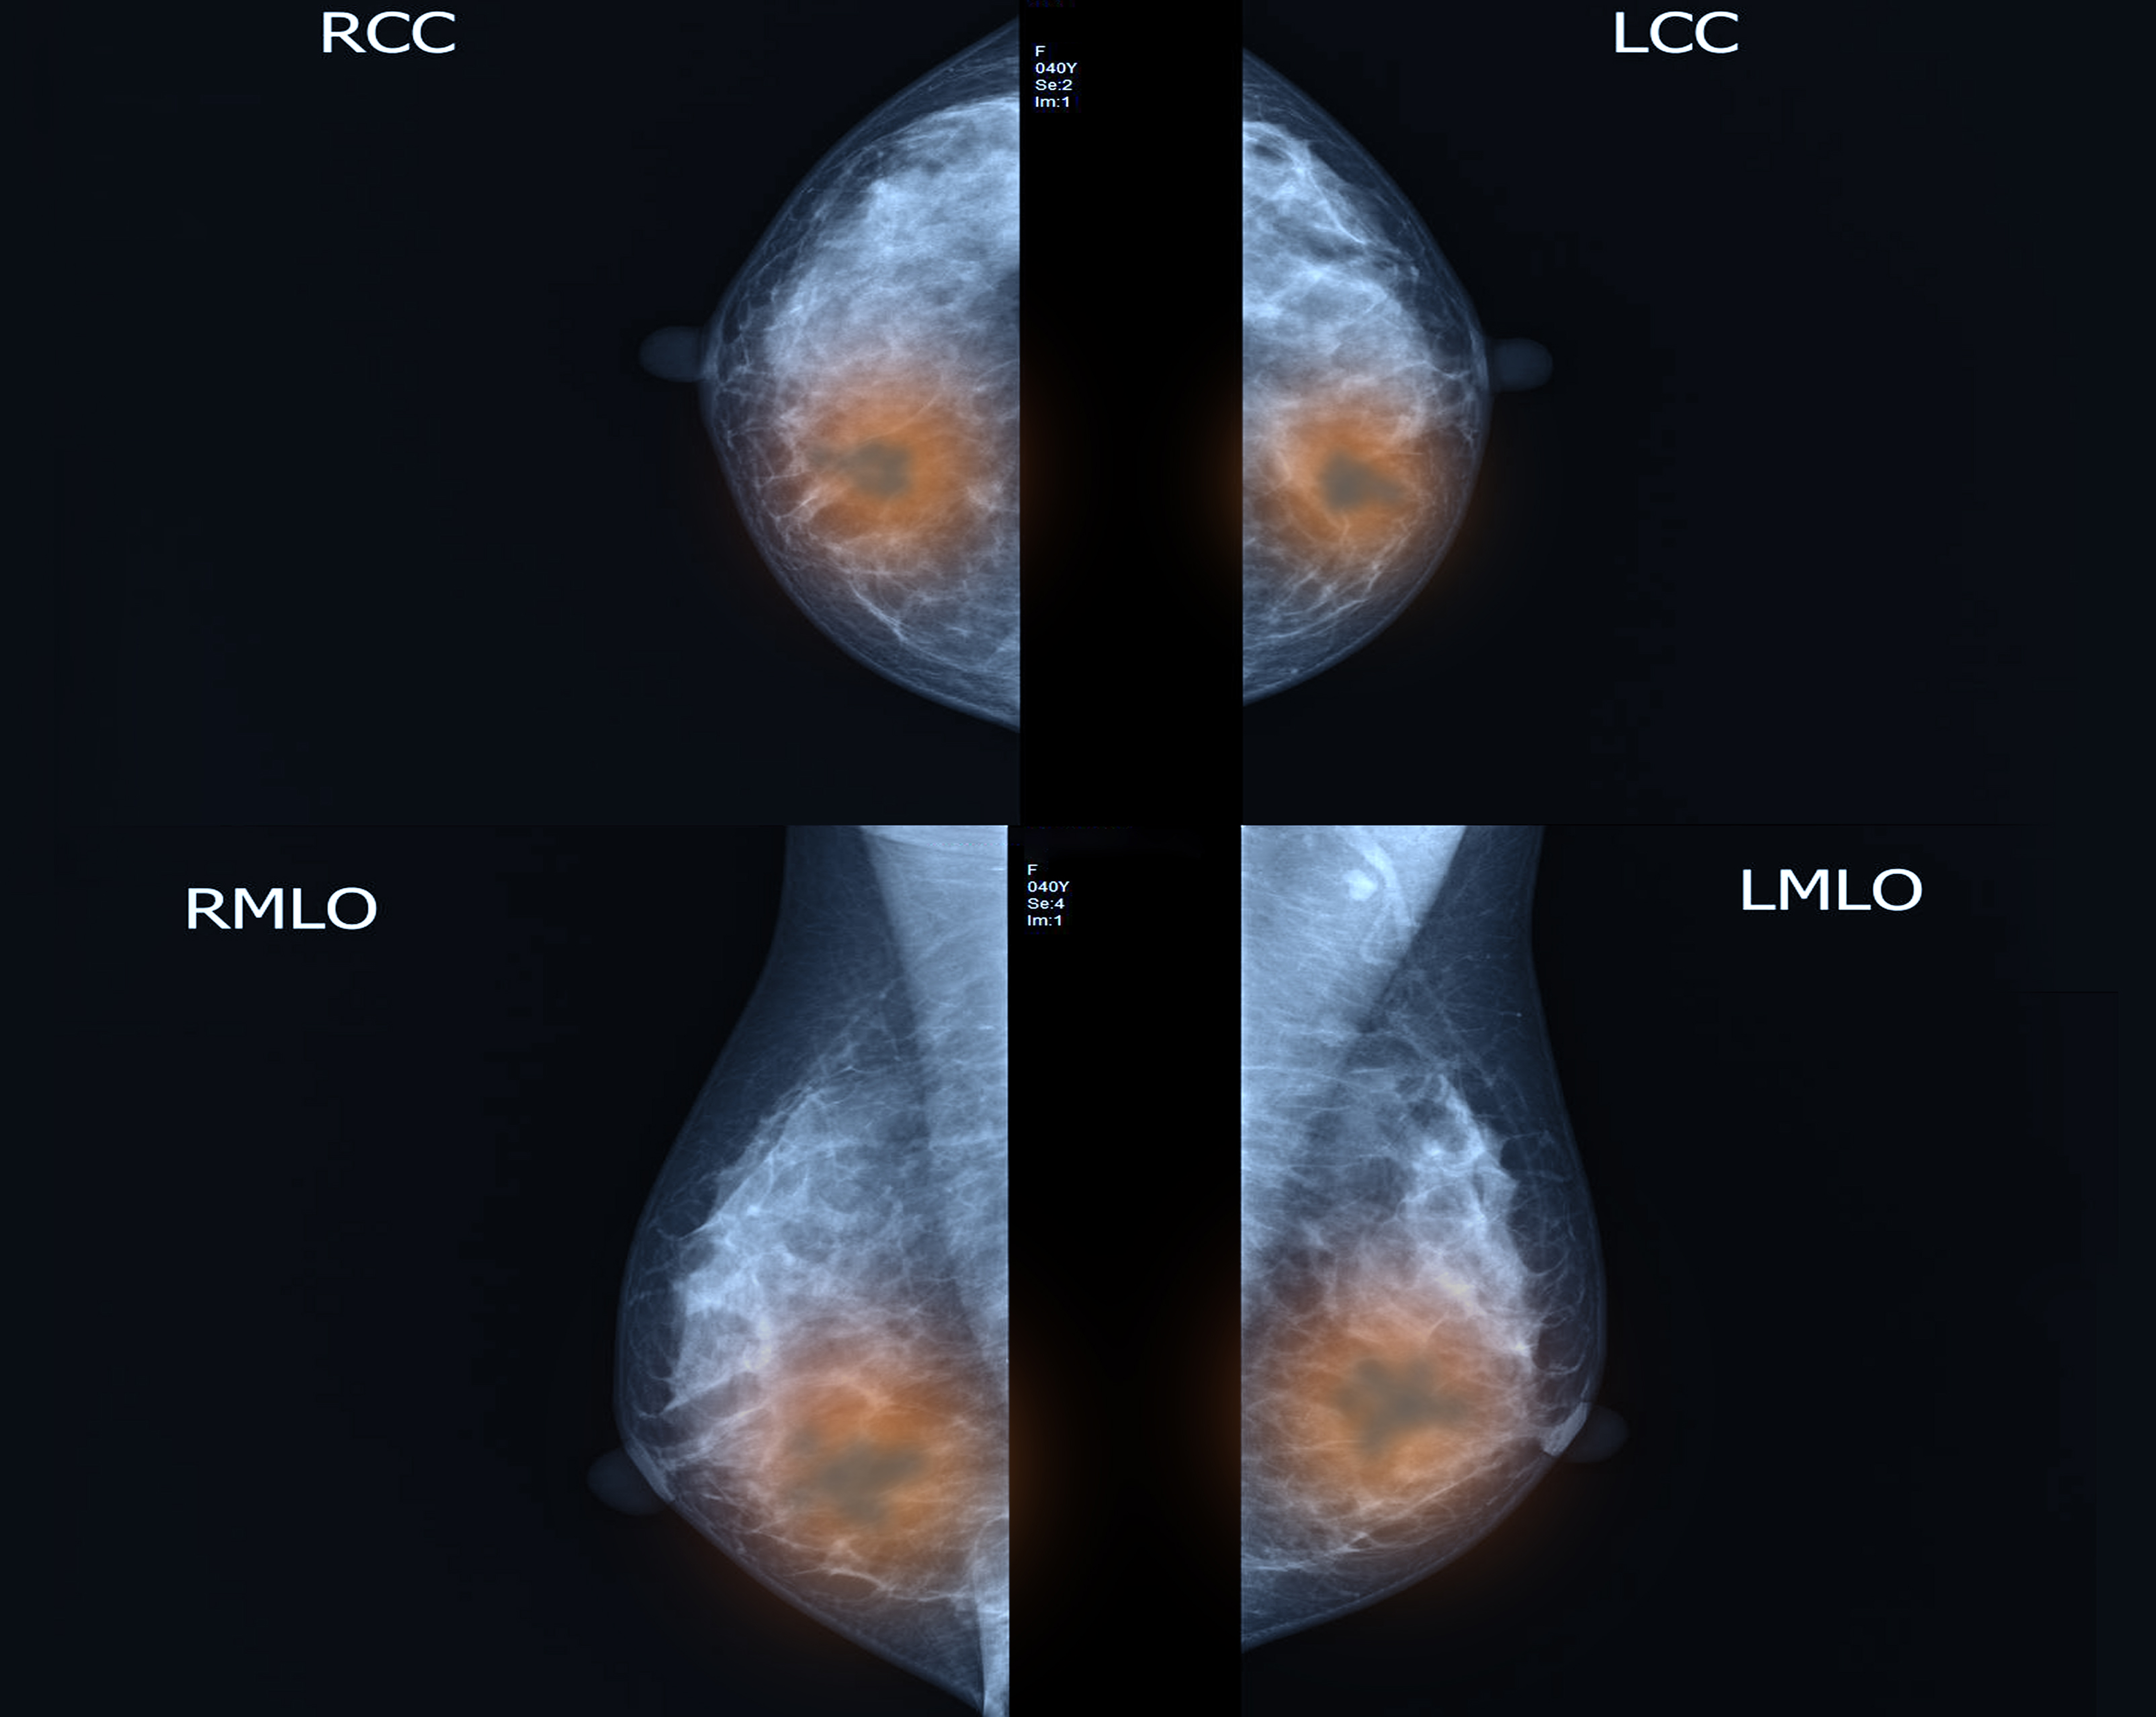

[Figuur 2] toont voor alle kankersoorten het aandeel van tijd gespendeerd bij de huisarts (HI), voor de verschillende kwartielen van de totale DI-duur. Voor colorectale kanker neemt bij een langere duur van het diagnostisch interval de proportie gespendeerde tijd bij de huisarts toe.

Figuur 2 | Het aandeel van het huisartsinterval, als percentage van de totale duur van het diagnostisch traject